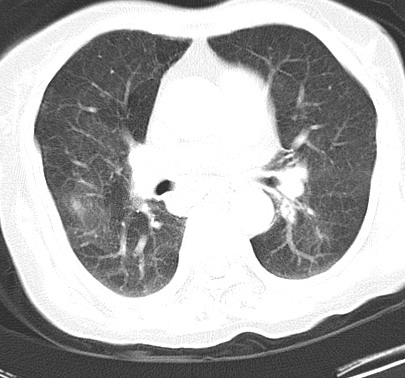

以下是引用hhcckk在2007-3-2 14:51:00的发言:[br]考虑结核球可能性大,依据[br]1病灶在下叶背段,结核的好发部位[br]2病灶内有大量的钙化,纵隔内有大量的淋巴结钙化[br]3重要的是半年前与现在相比无变化,假如是肿瘤的话不会这么‘善良’[br]4病灶周围卫星灶不明显,病灶有毛刺,胸膜凹陷,肿瘤不能完全排除,有条件的话最好做个活检

以下是引用liuyue在2007-3-2 17:15:00的发言:[br]1位置:右上叶后段[br]2性质:大分叶、粗长毛刺、条状斑片状钙化、纵隔多发淋巴结钙化,无强化,故考虑:肺结核灶(陈旧)